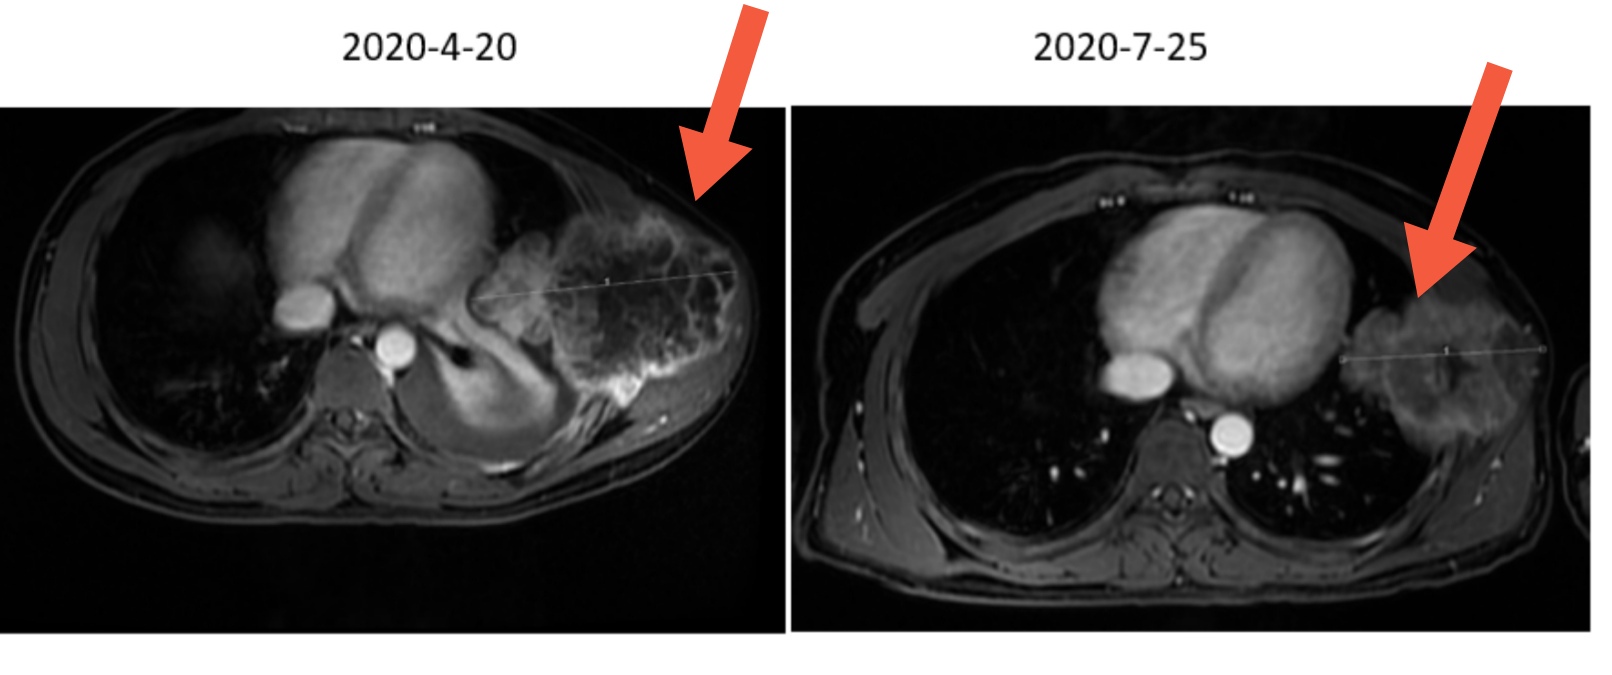

时间就是生命,治疗早一分,挽救患者生命的机会就多一分!诊断明确后,立即对毛先生进行了骨肉瘤的新辅助化疗,短短3个月后,症状完全缓解,肿瘤也较化疗前明显缩小。毛先生终于看到了生存的希望。

新辅助化疗前后对比